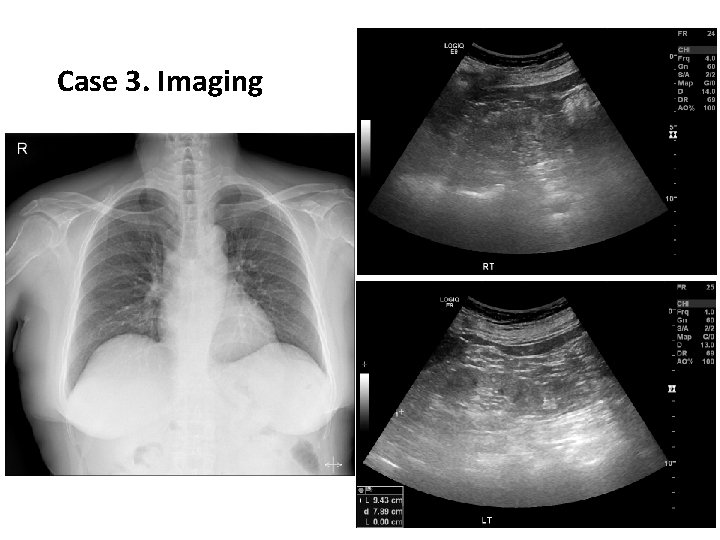

Case 3. Presentation • 62세 여성이 신장 기능 저하를 걱정하여 왔다. • 과거력: 고혈압 • 수술력: 슬관절치환(좌측), 백내장 • 약물력: valsartan 160, thiazide 12. 5, amlodipine 5 mg, febuxostat 40 mg, kremezin, kayexalate, ferrous sulfate BP 166/80 mm. Hg PR 95 /min Body weight 50 kg

Case 3. Imaging